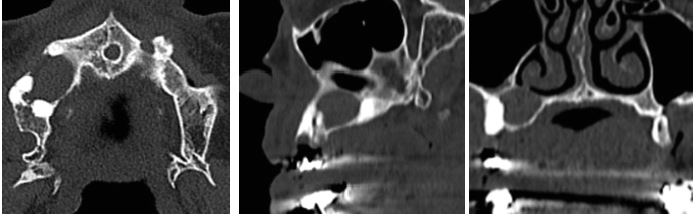

La tomografía helicoidal multicorte revela calcificación de la hoz del cerebro (figura 4), costilla bífida (figura 5). A nivel de los maxilares se observa imagen isodensa localizada en maxilar superior derecho, de forma ovalada, bordes definidos y corticalizados, presentando el adelgazamiento de la cortical ósea vestibular. Descripción imagenológica compatible con QQO (figura 6).